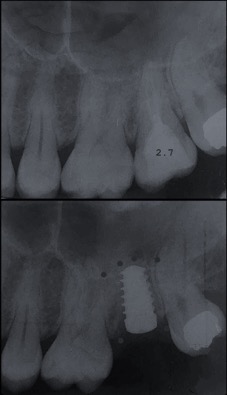

Un impianto dentale o fixture è un corpo in titanio, totalmente biocompatibile, che viene posizionato nella mascella o mandibola con lo scopo di sostituire la radice di un dente naturale perso. Su di esso viene successivamente o immediatamente quando possibile (carico immediato) fissata la protesi ovvero la corona del dente restituendo funzione ed estetica.

Con l’implantologia oggi è possibile sostituire un solo dente come un’intera arcata anche in casi di deficit ossei grazie alla GBR (rigenerazione ossea guidata) che ci permette di intervenire quando la disponibilità ossea iniziale del paziente non sarebbe sufficiente.

Una fixture collocata da un operatore esperto ha una percentuale di successo a 10 anni maggiore del 90%. È una delle percentuali in medicina più alte, chiaramente quando eseguita da mani competenti e con protocolli adeguati.